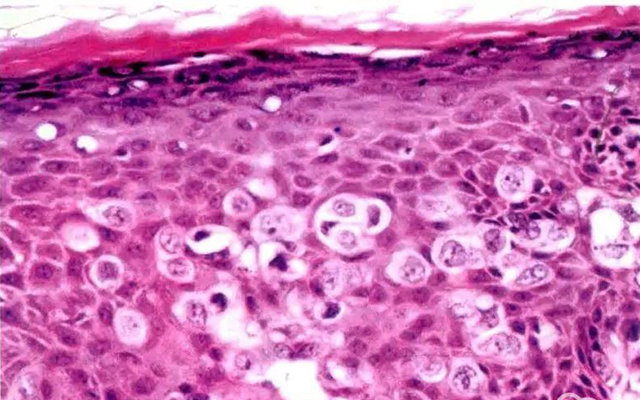

我们常说的过敏大多都有致敏原,比如皮肤瘙痒、*麻疹荨**等,一般表现为皮肤损伤。而过敏性紫癜并不是过敏导致的,它是一种变态反应毛细血管炎,患者一般会在紫癜出现前1-3周有低热、呼吸道感染等表现。

如果还不好理解的话,我们可以把常见的过敏当作是皮肤病,而过敏性紫癜是一种血管炎疾病,两者的发病机制和临床表现截然不一样。

过敏性紫癜的临床表现,除了四肢对称分布的红点红斑皮疹外,还会出现腹痛、恶心呕吐、关节肿痛、小便潜血、尿蛋白等表现。绝大多数患者首发症状是皮疹,而后出现其他表现,也有少部分患者首发症状是腹痛、关节肿痛表现,很容易造成误诊漏诊。